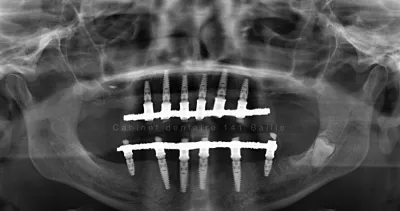

Implantologie Marseille-Dr TOURROLIER Didier .141 Bd Baille 13005

Aujourd'hui la pose d'un implant dentaire pour remplacer une dent est la technique incontournable.Les appareils amovibles et les Bridges dentaires ne sont plus d'actualité.L'implant dentaire est une racine artificielle placée directement dans l'os en lieu et place de la dent absente...

Le cabinet du Docteur Tourrolier Didier se trouve dans le centre-ville de Marseille (13006). La première activité du cabinet est la parodontie. En effet, l’équipe du Docteur Tourrolier est formée à la parodontologie pour traiter vos maladies, infections et inflammations des gencives. Parmi les techniques employées, nous retrouvons le surfaçage radiculaire et les greffes osseuses et gingivales. Pour remplacer les dents infectées ou fracturées, le Docteur Tourrolier pratique la pose d’implants dentaires (couronne, bridge).